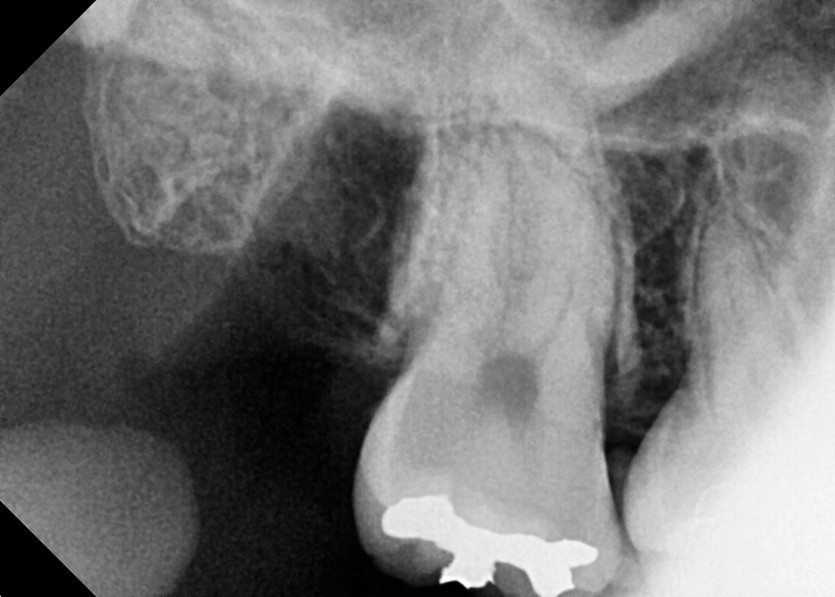

#18,48 사랑니 발치

구강 외과 전문의가 당일 발치했습니다.